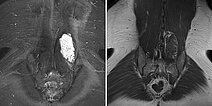

The lesion is very clearly visible in the MRI in coronal plane. In the T2-weighted sequence with fat saturation (left), the lesion is highly hyperintense (white). In the non-enhanced T1-weighted sequence (right), it is virtually isointense to the surrounding back muscle. Note here the fatty tissue visible marginally in the lesion, hyperintense in T1 weighting.

In the axial T2-weighted MRI sequence, the lesion is located in the erector spinae back muscles. Classic fluid-fluid level due to gravity-induced sedimentation effects with the patient lying still in the supine position in the MRI unit.